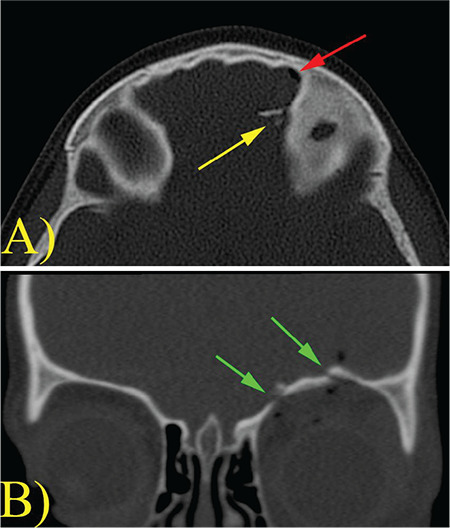

一名 4 岁男孩被一只大型犬刺伤左眼眶,随后被转诊到我们的三级医院。当时流泪增多,原以为是炎症反应所致。然而,研究人员发现,泪液在反滕卧位和做瓦尔萨尔瓦动作时会增多。光环征和β转铁蛋白试验均呈阳性,因此诊断为脑脊液(CSF)瘘,患者接受了眶上开颅手术。手术中发现了硬脑膜撕裂并进行了适当缝合,然后在撕裂处应用了纤维蛋白胶和自体硬脑膜移植。术后脑脊液渗出停止,随访 10 天后患者出院。在 4 年的随访中,患者没有再出现 CSF 渗漏。虽然 CSF 渗漏很少见,而且可能很难从流泪中辨别出来,但如果出现气胸和晕轮征,则应考虑瘘管修补术。

A 4-year-old boy was referred to our tertiary hospital after a penetrating adnexal injury by a large-breed dog to the left orbital area. There was an increase in lacrimation, which was thought to be due to an inflammatory reaction. However, it was discovered that the lacrimation increased in the reverse-Trendelenburg position and with the Valsalva maneuver. Halo sign and beta transferrin test were positive, which led to the diagnosis of cerebrospinal fluid (CSF) fistula, and the patient was operated using a supraorbital craniotomy. A dural tear was visualized and sutured appropriately, then fibrin glue and an autologous galeal graft were applied to the tear. The CSF oculorrhea stopped postoperatively, and the patient was discharged after 10 days of follow-up. The patient had no recurrent CSF leakage at 4-year follow-up. Although CSF oculorrhea is rare and may be difficult to discern from lacrimation, the presence of pneumocephalus and halo sign should suggest fistula repair.